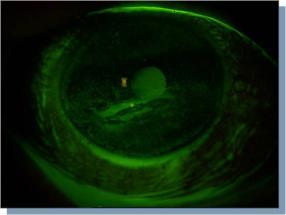

Terugkomend op de meerkeuzevraag van deze maand: pas als de laag onder dit basaalmembraan is

aangetast, het membraan van Bowman dus, dan kan er fibrosevorming (littekenvorming) ontstaan in de

cornea. Indien dit gebeurt, ‘zuigt’ de fluoresceïne zich in het stroma en is er doorgaans een ‘wolk’ van

fluoresceïne te zien rondom het aangedane gebied. Maar zolang de staining epitheliaal van aard is, is er

dus geen risico op littekenvorming - onafhankelijk van het type (micropunctata, macropunctata) staining,

de grootte van de oppervlakte waarover de staining zich bevindt en de duur van de aanwezigheid van

staining.